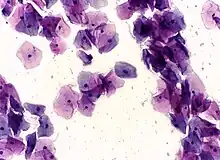

Micrograph of a normal pap smear

Pap tests commonly examine epithelial abnormalities, such as metaplasia, dysplasia, or borderline changes, all of which may be indicative of CIN. Nuclei will stain dark blue, squamous cells will stain green and keratinised cells will stain pink/ orange. Koilocytes may be observed where there is some dyskaryosis (of epithelium). The nucleus in koilocytes is typically irregular, indicating possible cause for concern; requiring further confirmatory screens and tests.